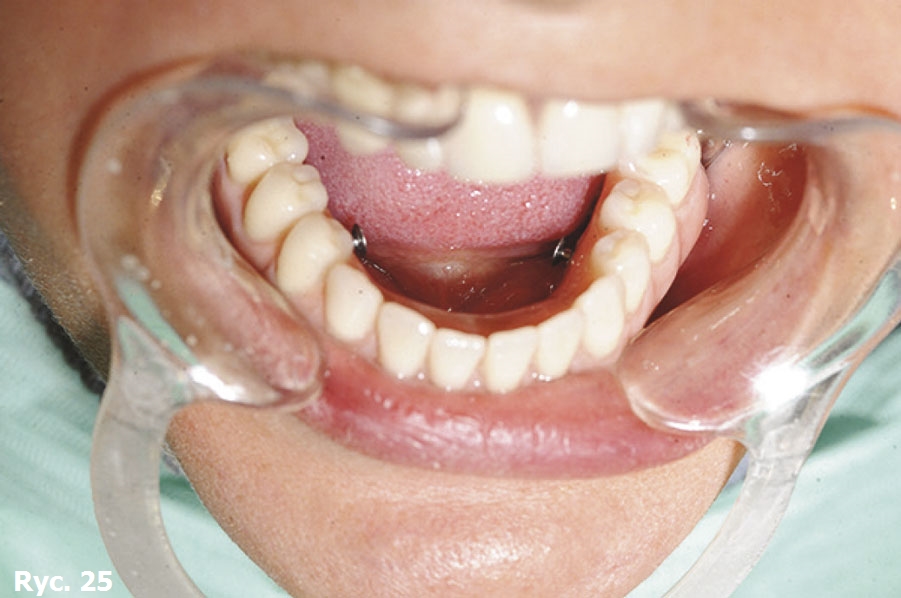

Pacjentkę poinformowano, że jedyną metodą leczenia, która jej pozostała, jest zastosowanie wszczepu podokostnowego. Skierowano ją do Turynu, do dr. G. Cortese. Po analizie badania TK oraz modelu stereolitograficznego doktor G. Cortese zdecydował, że najbardziej odpowiednim wszczepem, który rozwiąże problemy pacjentki, będzie trzyczęściowy implant podokostnowy Linkowa. Zarówno zabieg chirurgiczny, jak i wykonanie ostatecznego uzupełnienia protetycznego przebiegły bez większych problemów (ryc. 23, 24).

Po oddaniu protezy objawy depresji ustąpiły, pacjentka szybko straciła zbędne kilogramy. Nowe uzupełnienie protetyczne zostało zakotwiczone i wsparte na trzyczęściowym wszczepie podokostnowym. Dzięki temu było bardzo stabilne i jednocześnie łatwe do zdejmowania, koniecznego do codziennych zabiegów higienizacyjnych (ryc. 25, 26, 27)